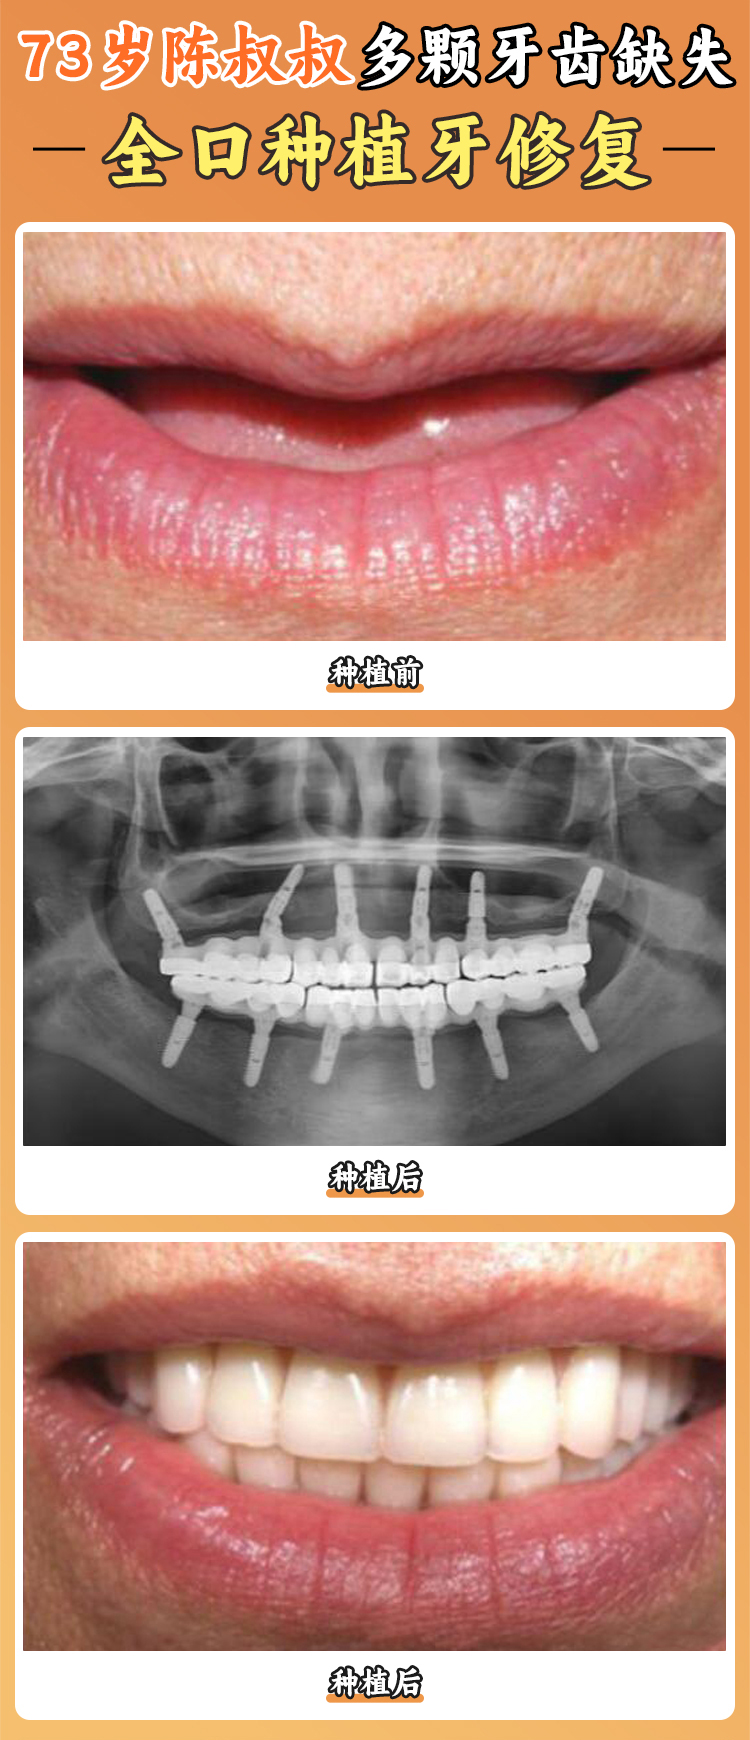

即刻負(fù)重技術(shù)(All - on - 4/6)也特別厲害,對(duì)于半口或全口牙齒缺失的患者,僅需植入4 - 6顆種植體,當(dāng)天就能佩戴臨時(shí)牙冠,還能嘗試進(jìn)食,縮短了無牙等待期,快速改善了咀嚼功能和面部外觀。

醫(yī)院具備復(fù)雜病例診療能力,可開展穿顴骨種植、穿翼板種植、上頜竇提升術(shù)、GBR骨增量等骨增量手術(shù),能解決牙槽骨萎縮、骨量重度不足等疑難種植需求。

半口/全口種植牙的收費(fèi)也有多種選擇。半口韓國(guó)進(jìn)口植體種植牙19600元起,半口瑞典諾貝爾植體種植牙39600元起,全口韓國(guó)進(jìn)口植體種植牙39800元起,全口高端植體種植牙79800元起,半口即刻種植60000 - 120000元,全口ALL - ON - 4種植100000 - 200000元,全口種植套餐(含純鈦橋架)4萬元起,瑞典諾貝爾全口種植8萬元起。

汪龍河是種植院長(zhǎng),深耕種植領(lǐng)域18年以上,累計(jì)完成種植手術(shù)超5000例,種牙患者回訪滿意度達(dá)98%。他擅長(zhǎng)數(shù)字化微創(chuàng)口腔種植、半口/全口種植、上頜竇內(nèi)/外提升、穿翼板種植技術(shù)、ALL - ON - 4/6即刻拔牙/種植/修復(fù)、骨增量、全口咬合重建,10年植體存活率達(dá)95%以上。